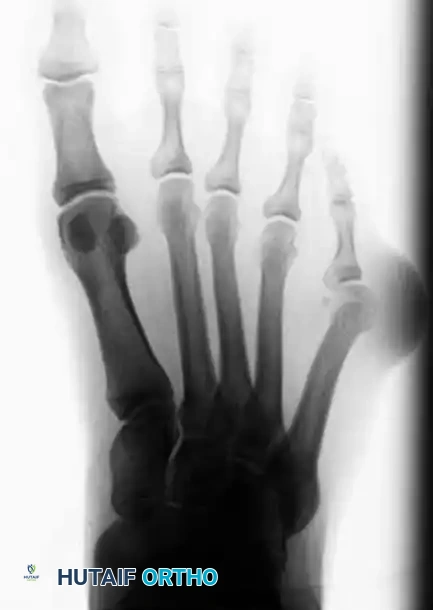

Radiographic Evaluation

Standard weight-bearing anteroposterior (AP), lateral, and oblique radiographs of the foot are mandatory for the accurate assessment of a bunionette deformity. The AP radiograph is utilized to measure several critical angles that dictate surgical decision-making.

Key Radiographic Parameters

- 4-5 Intermetatarsal Angle (IMA): Formed by the intersection of the longitudinal axes of the fourth and fifth metatarsals.

- Normal: Less than 8 degrees.

- Pathologic: Greater than 8 degrees indicates pathological divergence of the fifth ray.

- Fifth Metatarsophalangeal (MTP-5) Angle: Formed by the longitudinal axis of the fifth metatarsal and the longitudinal axis of the proximal phalanx of the fifth toe.

- Pathologic: Usually greater than 14 degrees in symptomatic patients.

FIGURE 83-40 Measurement of metatarsophalangeal-5 and 4-5 intermetatarsal angles for evaluation of bunionette deformity.

- Lateral Deviation Angle (LDA): This angle evaluates the intrinsic bowing of the fifth metatarsal shaft. It is formed by a line bisecting the metatarsal head and neck intersecting with a line drawn parallel to the medial cortex of the proximal fifth metatarsal shaft.

- Normal: Approximately 2.6 degrees.

- Pathologic: Averages 8 degrees in patients with a symptomatic bunionette.

FIGURE 83-42 Measurement of lateral deviation angle in the evaluation of bunionette deformity.